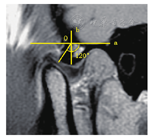

(3)髁突长轴及短轴:在闭口位横断面T2WI图像髁突最大长轴层面测量髁突内外极最大径(平行于髁突走形方向)长度即为髁突长轴,垂直于长轴的最大径(垂直于髁突走形方向)长度即为髁突短轴(图8A)。

(4)髁间角:在横轴位T2WI图像上,通过双侧髁突长轴延长线的夹角即为髁间角,髁间角的测量涉及双侧颞下颌关节(图8B)。